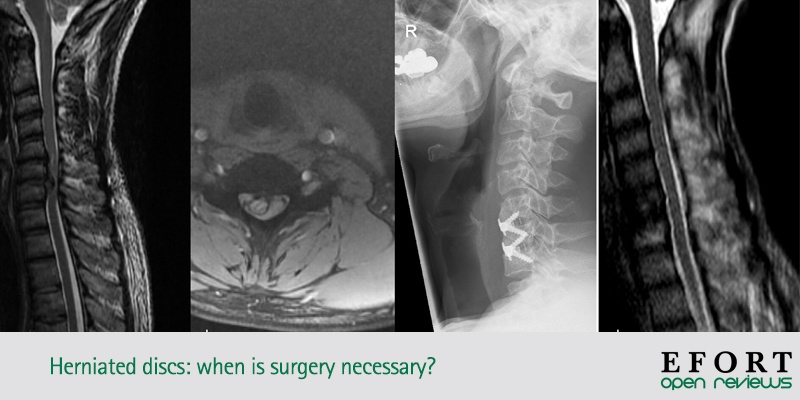

Discos herniados: ¿cuando es necesaria la cirugía?

- En todos los niveles de hernias de disco, las indicaciones quirúrgicas absolutas incluyen el deterioro de los déficits neurológicos con mielopatía o síndrome de cola de caballo. Sin embargo, esta revisión resumió las indicaciones relativas de la cirugía en cada nivel.

- En la hernia de disco cervical (HDC), las indicaciones de cirugía consisten en seis meses de síntomas persistentes, sin respuesta al tratamiento conservador. Sin embargo, faltan estudios de alta calidad y ahora se está llevando a cabo un ensayo controlado aleatorio para aclarar las indicaciones.

- En la hernia de disco torácico (TDH), las indicaciones para la cirugía comprenden el fracaso de las medidas conservadoras y / o el empeoramiento de los síntomas neurológicos. Además, las hernias gigantes calcificadas de disco torácico o los signos de mielopatía en la resonancia magnética, incluso en ausencia de síntomas neurológicos, pueden beneficiarse del tratamiento quirúrgico como medida preventiva.

- En la hernia de disco lumbar (LDH), las indicaciones para la cirugía incluyen la confirmación por imágenes de la LDH, consistente con los hallazgos clínicos, y la falta de mejoría después de seis semanas de cuidados conservadores.